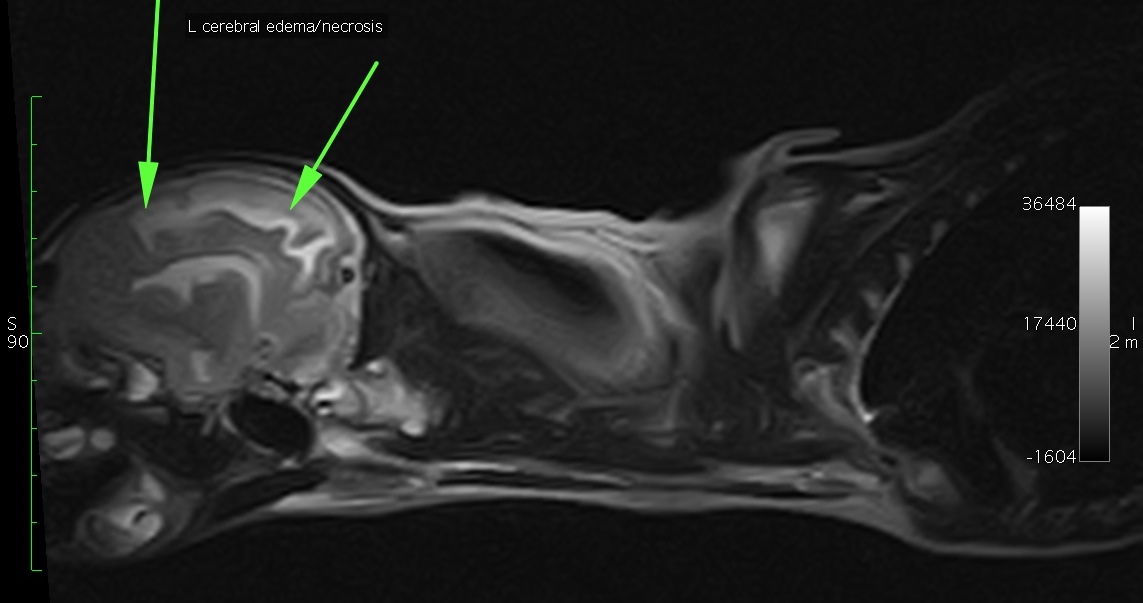

Once Khloe was stable, she was transported to get an MRI of her head and neck.

When the MRI report arrived, we were shocked.

Khloe had several skull fractures, with severe changes in her brain, including encephalitis (irritation of the brain) and too much fluid. It was suspected to be due to an infection, most likely caused by the dog bite.

In addition, a brain abscess was suspected.

She had a mild displacement (hernia) of the back of her brain, called the cerebellum. And she had a severe syringomyelia extending caudally to the 8th thoracic vertebra (ie the middle of the chest).